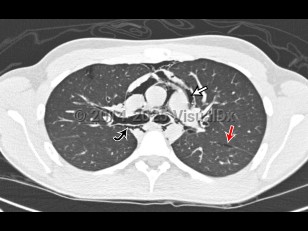

Pneumomediastinum is the presence of air in the mediastinum. It is caused by injury, most often esophageal or intestinal perforation. It can rarely occur spontaneously in children with acute asthma attacks (severe cough) and is also seen as a result of aggressive bag-valve mask ventilation during resuscitation and intubation as well as a result of barotrauma in intubated patients.